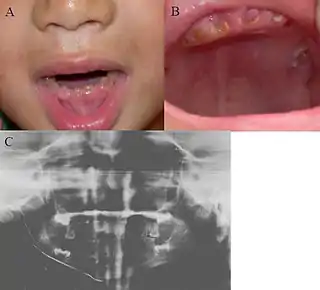

![]() Imagen clínica de la dentinogénesis Imperfecta y Ortopantomografía]] | ||

Desde el punto de vista clínico, los tres tipos comparten diversas características, en ambas denticiones, se muestra un aspecto opalescente, con una translucidez rara y de color que varía del café amarillo al gris azulado. Toda la corona manifiesta cambio de coloración debido a la dentina anormal subyacente. A pesar de que el esmalte es normal tanto en su estructura como en su composición química se fractura con facilidad, al parecer se debe al soporte deficiente que proporciona la dentina anormal.

La morfología dental en general es rara ya que hay una constricción excesiva en la unión esmalte cemento, lo que le da a la corona forma de campana; las raíces son cortas y romas; los dientes no presentan aumento en la susceptibilidad a la caries y si en cambio puede mostrar cierta resistencia a esta por el desgaste rápido y la ausencia de túbulos dentinarios.

Características Radiográficas

Radiográficamente la D.I. se caracteriza por la presencia de dientes con coronas bulbosas, con una constricción en el cuello y raíces cortas y delgadas. Se observa obliteración precoz, parcial o total de las cámaras pulpares por la formación continua de dentina. Estas características se presentan tanto en la dentición temporal como permanente. Frecuentemente se observan fracturas radiculares múltiples, en particular en personas de edad. El cemento, la membrana periodontal y el hueso alveolar aparecen normales. Estas características son comunes para la D.I. tipo I y II mientras que en la tipo III la dentina aparece delgada, las cámaras pulpares y conductos radiculares son muy grandes y dan la apariencia de conchas delgadas de dentina, razón por lo que se llama a esta entidad "dientes en concha". Adicionalmente se presentan exposiciones pulpares múltiples y radiolucencias periapicales.